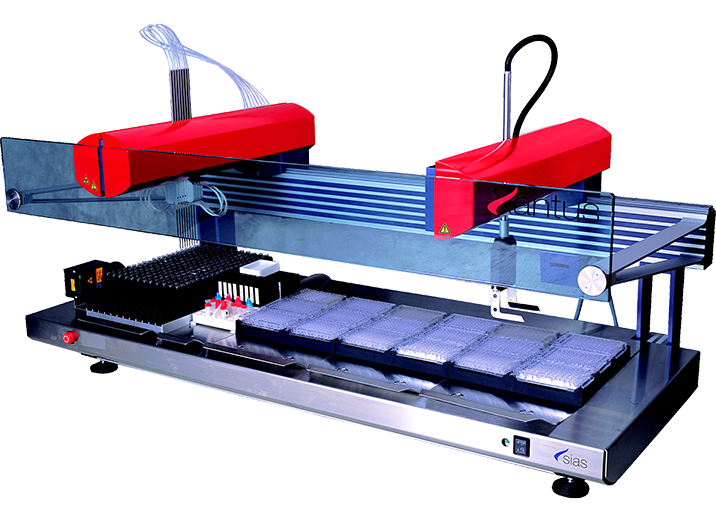

Xantus全自动加样系统是爱康从瑞士Sias合作引进的一款高性能全自动加样器。爱康在原装进口优质加样平台的基础上,充分发掘产品潜力,淋漓尽致的展现其性能优势。

7min可实现88个标本的血筛四项标本平行分配,适用于各类血液机构

全自动加样器可一次性上样192个标本,在试验过程中可循环进样,连续的卸载、装载试管,实现流水线式工作

Xantus全自动加样器在使用一次性针时,采用一次性加样针,拖带污染为0

简洁的管路和泵阀组成,是保证仪器稳定性和加样准确度的重要因素

Xantus系列目前拥有三种型号可供选择,满足不同的临床需求